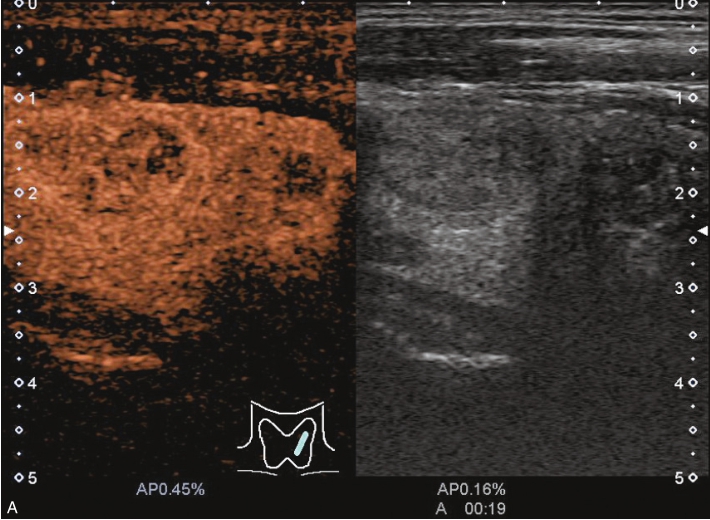

经肘正中静脉团状注射造影剂SonoVue1.2ml后,13s周围甲状腺组织开始增强,病灶边缘部呈稍增强,病灶内部始终呈无增强,在整个造影过程中病灶内始终呈无增强,见图1-3-12、ER1-3-6。

“木乃伊”结节超声造影表现为无增强。

部分良性甲状腺结节囊液吸收后超声表现为低回声、缩小,超声表现为可疑恶性征像,二维超声表现与甲状腺乳头状癌难以鉴别,超声造影可以明确病灶内有无增强,提高诊断准确性。

图1-3-12 甲状腺“木乃伊”结节造影图像

A.造影示低回声结节呈无增强;B.增强晚期仍呈无增强